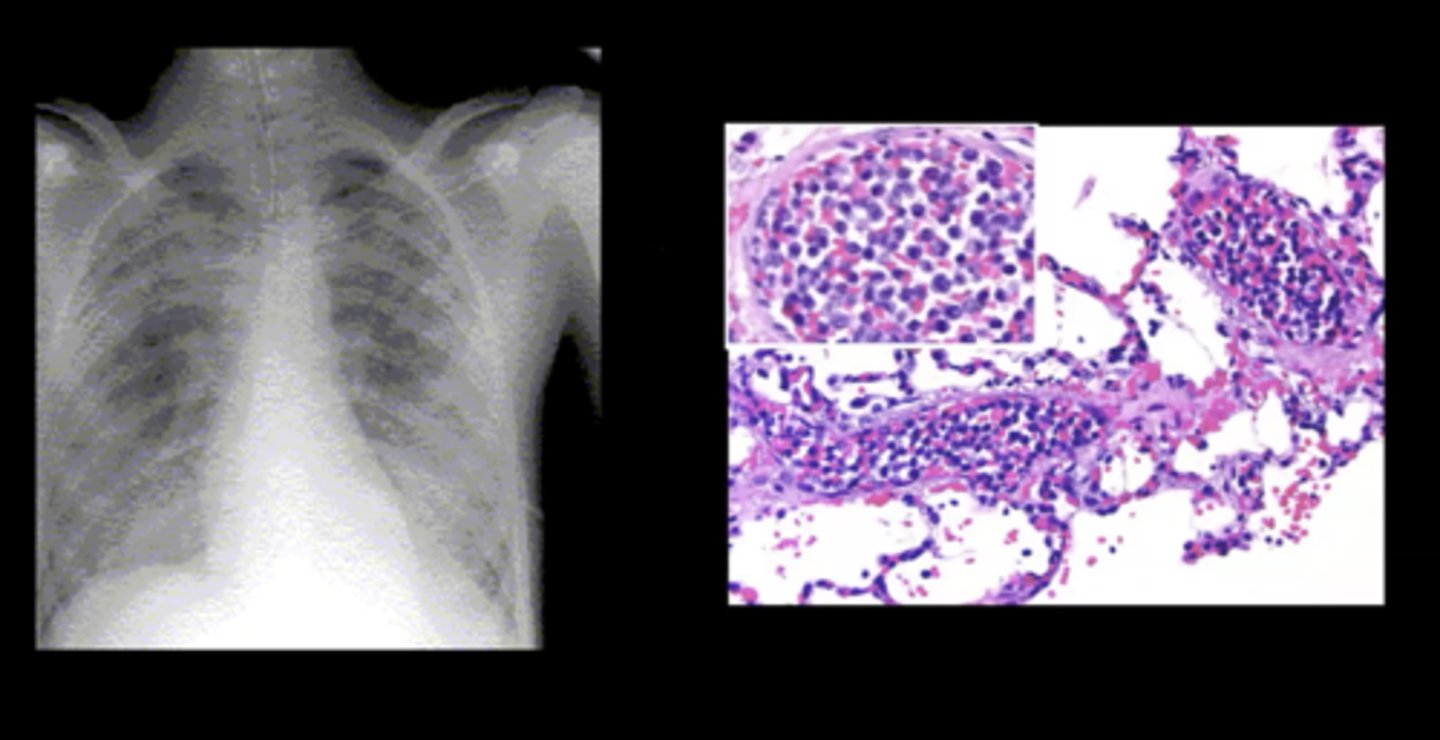

Leukostasis

Complication of acute leukemia; a severely elevated circulating immature WBC count --> blood is more viscous --> clot development

Pulmonary leukostasis

Sudden shortness of breath and progressive dyspnea; caused by a WBC clot

Leukemias

Cancers of the hematopoietic stem cells in the bone marrow

Acute Leukemias

Large numbers of immature BLAST leukocytes in the blood and bone marrow (rapid onset and progression)